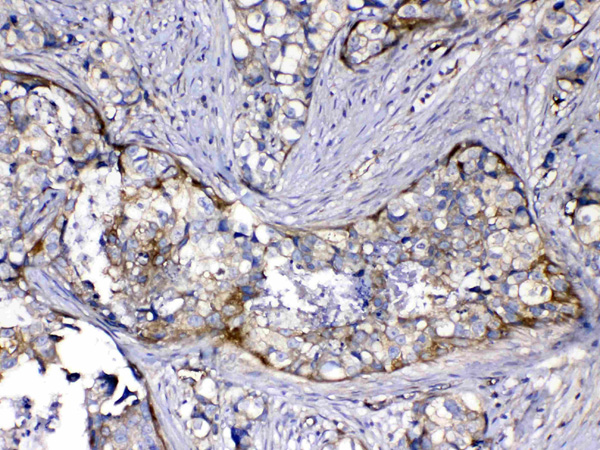

IHC (Immunohistochemistry)

(Figure 4. IHC analysis of HOMER3 using anti-HOMER3 antibody (AAA124742).HOMER3 was detected in paraffin-embedded section of human mammary cancer tissue. Heat mediated antigen retrieval was performed in citrate buffer (pH6, epitope retrieval solution) for 20 mins. The tissue section was blocked with 10% goat serum. The tissue section was then incubated with 1ug/ml rabbit anti-HOMER3 Antibody (AAA124742) overnight at 4 degree C. Biotinylated goat anti-rabbit IgG was used as secondary antibody and incubated for 30 minutes at 37 degree C. The tissue section was developed using Strepavidin-Biotin-Complex (SABC) with DAB as the chromogen.)